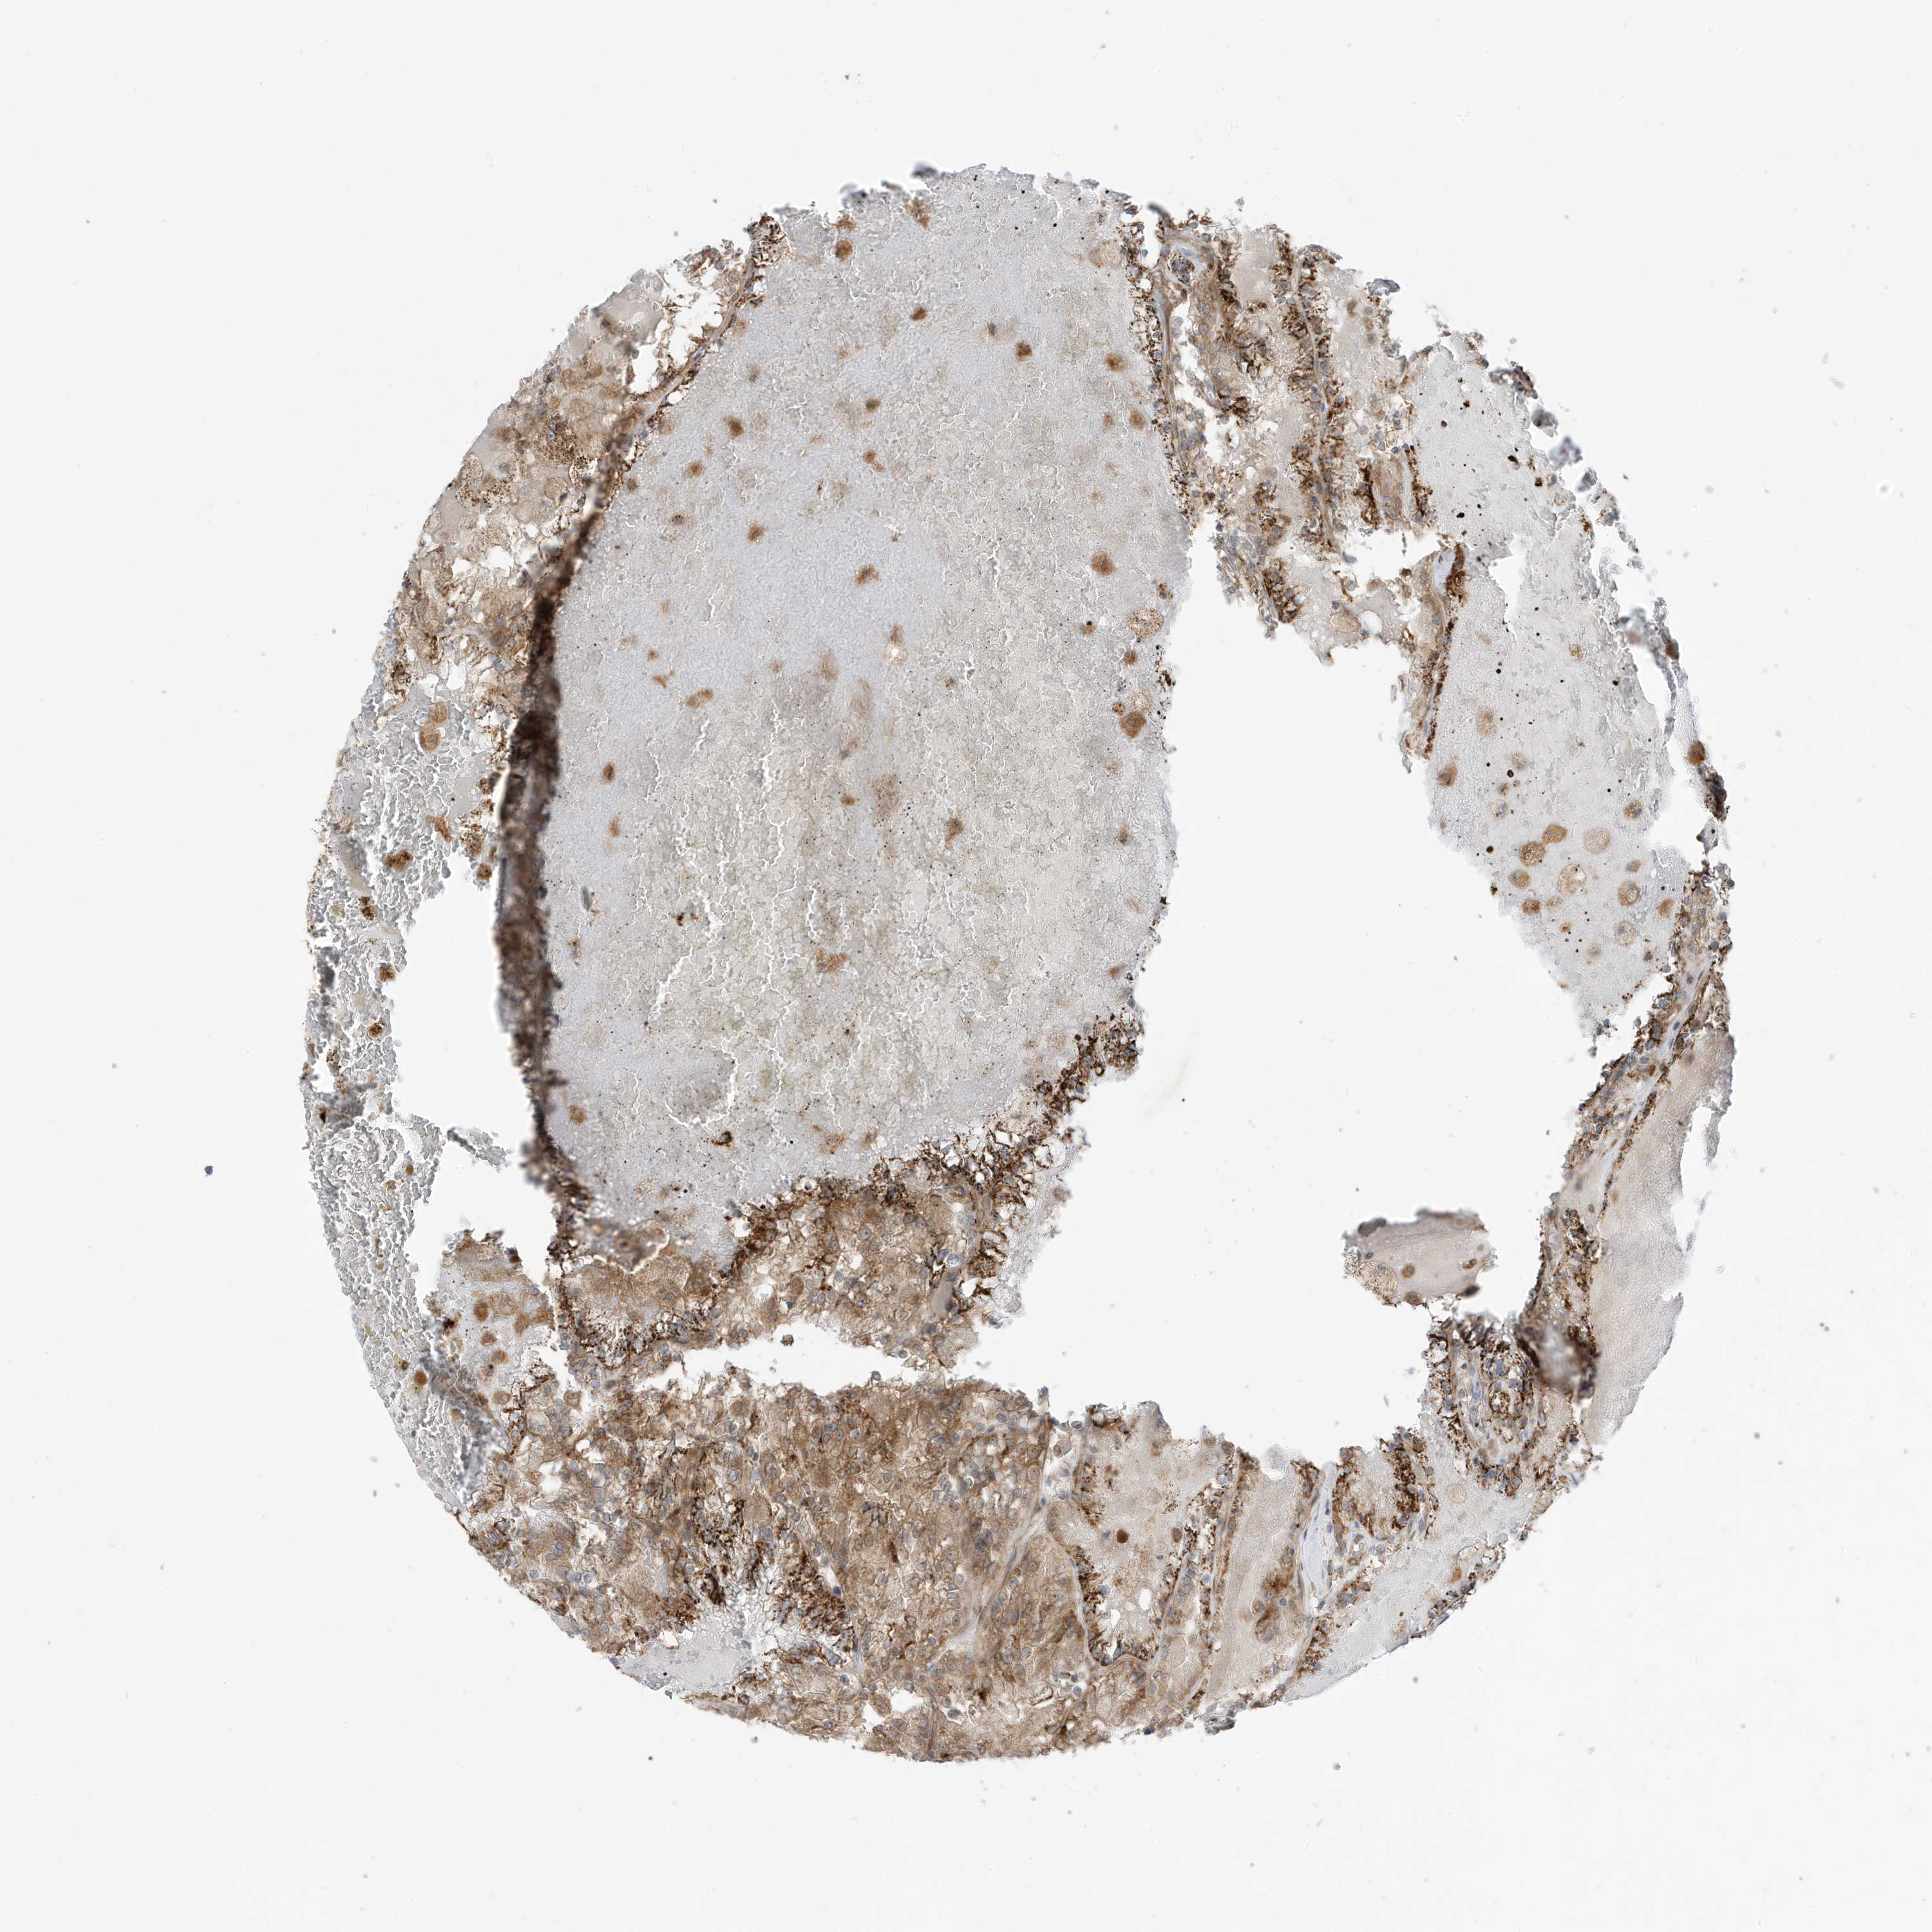

KIDNEY RENAL CLEAR CELL CARCINOMA (VALIDATION) - Interactive survival scatter ploti

The Survival Scatter plot shows the clinical status (i.e. dead or alive) for all individuals in the patient cohort, based on the same data that underlies the corresponding Kaplan-Meier plots. Patients that are alive at last time for follow-up are shown in blue and patients who have died during the study are shown in red.

The x-axis shows the expression levels (FPKM) of the investigated gene in the tumor tissue at the time of diagnosis. The y-axis shows the follow-up time after diagnosis (years). Both axes are complimented with kernel density curves demonstrating the data density over the axes. The top density plot shows the expression levels (FPKM) distribution among dead (red) and alive patients (blue). The right density plot shows the data density of the survived years of dead patients with high and low expression levels respectively, stratified using the cutoff indicated by the vertical dashed line through the Survival Scatter plot. This cutoff is automatically defined based on the FPKM cutoff that minimizes the p-score. The cutoff can be changed by dragging the vertical line or by entering a cutoff value in the square labeled "Current cut-off".

Under the Survival Scatter plot the p-score landscape (black curve; left axis) is shown together with dead median separation (red curve; right axis). Dead median separation is the difference in median mRNA expression between patients who have died with high and low expression, respectively. It is calculated as follows: median FPKM expression of dead patients with high expression - median FPKM expression of dead patients with low expression. This is intended to aid the user in visually exploring custom cutoffs and the associated p-scores and dead median separation.

Individual patient data is displayed and can be filtered by clicking on one or more of the category buttons on the top of the page. Categories describing expression level and patient information include: high, low, alive, dead, female, male and tumor stages. The scale of the x-axis can be toggled between linear and log-scale by clicking on the "x log" button. Mouse-over function shows TCGA ID, patient information and mRNA expression (FPKM) for each patient.

& Survival analysisi

Kaplan-Meier plots summarize results from analysis of correlation between mRNA expression level and patient survival. Patients were divided based on level of expression into one of the two groups "low" (under cut off) or "high" (over cut off). X-axis shows time for survival (years) and y-axis shows the probability of survival, where 1.0 corresponds to 100 percent.

DHX36 is not prognostic in Kidney Renal Clear Cell Carcinoma (validation)

Best expression cut offi

Based on the FPKM value of each gene, patients were classified into two groups and association between prognosis (survival) and gene expression (FPKM) was examined. The best expression cut-off refers the FPKM value that yields maximal difference with regard to survival between the two groups at the lowest log-rank P-value. Best expression cut-off was selected based on survival analysis .

When clicking on this number, the vertical dashed line indicating cut-off, the interactive survival plot, and the Kaplan-Meier curve will be adjusted to show results based on the best expression cut-off.

: 24.15

P scorei

Log-rank P value for Kaplan-Meier plot showing results from analysis of correlation between mRNA expression level and patient survival.

N/A

TCGA RNA samplesi

RNA-seq data is reported as average FPKM (number Fragments Per Kilobase of exon per Million reads), generated by the The Cancer Genome Atlas (TCGA) .

Normal distribution across the dataset is visualized with box plots, shown as median and 25th and 75th percentiles. Points are displayed as outliers if they are above or below 1.5 times the interquartile range. FPKM values of the individual samples are presented next to the box plot.

Average pTPM 18.7

Number of samples 100